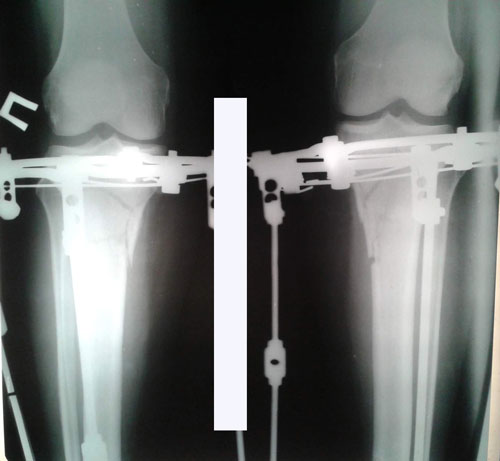

Дата операции 17.11.2015г.

Дата снятия аппаратов 10.02.2016г.

Срок лечения 85 дней.